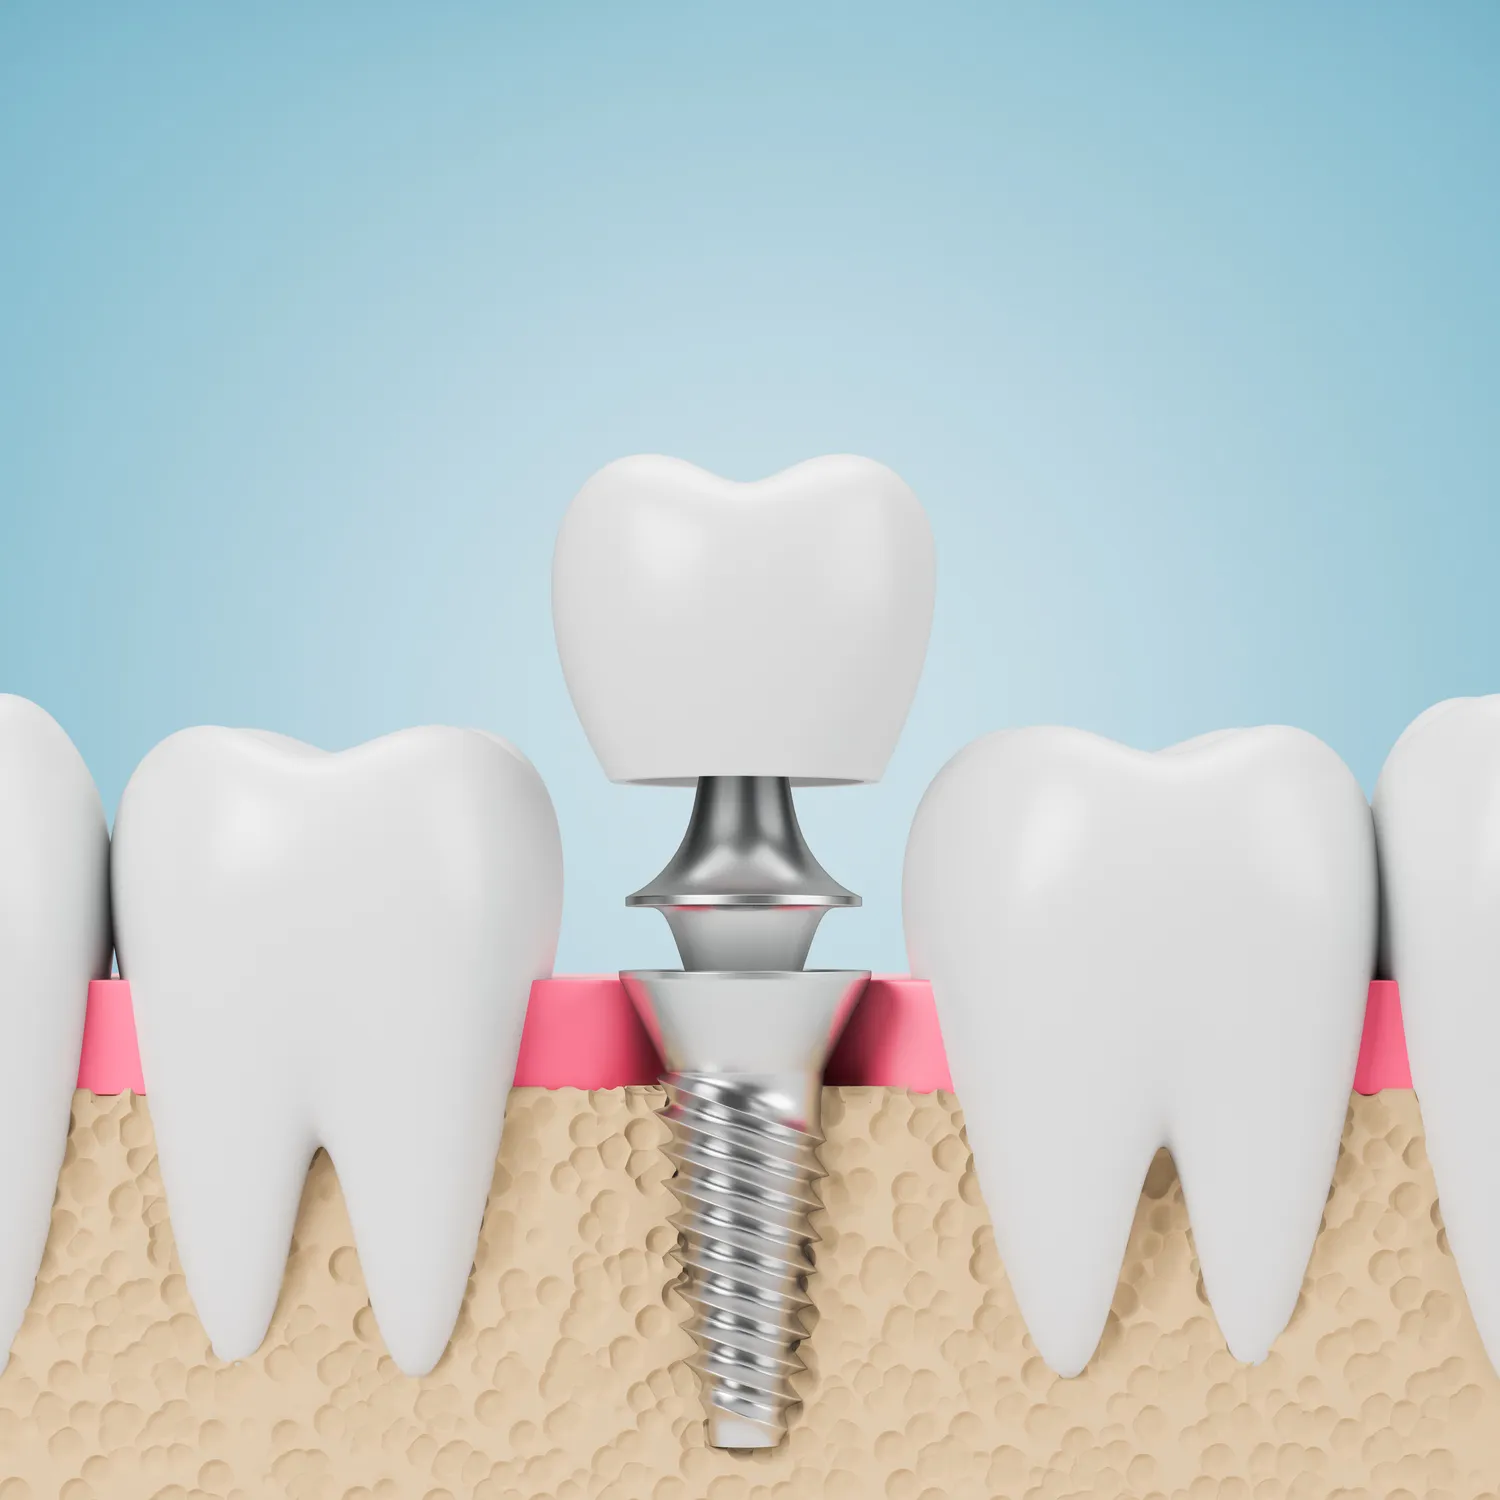

Implanty stomatologiczne w Szczecinie cieszą się rosnącą popularnością, a ich zalety przyciągają coraz więcej pacjentów. Przede wszystkim, implanty oferują trwałe i estetyczne rozwiązanie dla osób z brakującymi zębami. W przeciwieństwie do tradycyjnych protez, które mogą być niewygodne i wymagać częstej wymiany, implanty są osadzone w kości szczęki, co sprawia, że wyglądają i funkcjonują jak naturalne zęby. Dodatkowo, proces ich zakupu jest znacznie bardziej komfortowy, ponieważ nie wymagają one stosowania klejów ani innych środków mocujących. Kolejną istotną zaletą jest poprawa jakości życia pacjentów. Dzięki implantom można swobodnie jeść ulubione potrawy, mówić bez obaw o wypadnięcie protezy oraz cieszyć się pewnością siebie. Warto również wspomnieć o korzyściach zdrowotnych, jakie niesie ze sobą ich zastosowanie. Implanty pomagają w zachowaniu struktury kości szczęki, co zapobiega jej zanikowi, który często występuje po utracie zębów.

Zakup implantów stomatologicznych w Szczecinie to proces składający się z kilku kluczowych etapów, które mają na celu zapewnienie pacjentowi jak najlepszego efektu końcowego. Pierwszym krokiem jest konsultacja ze specjalistą, podczas której lekarz ocenia stan uzębienia oraz ogólny stan zdrowia pacjenta. W trakcie tej wizyty wykonuje się również zdjęcia rentgenowskie oraz inne badania diagnostyczne, które pozwalają na dokładne zaplanowanie zabiegu. Po ustaleniu wskazań do wszczepienia implantu następuje etap przygotowawczy. Może on obejmować leczenie kanałowe lub usunięcie zębów, które nie nadają się do dalszego użytkowania. Gdy wszystko jest gotowe, lekarz przystępuje do wszczepienia implantu. Zabieg ten zazwyczaj odbywa się w znieczuleniu miejscowym i trwa od jednej do kilku godzin w zależności od liczby wszczepianych implantów. Po zabiegu pacjent musi przestrzegać zaleceń lekarza dotyczących pielęgnacji jamy ustnej oraz diety, aby zapewnić prawidłowe gojenie się tkanek.

Wielu pacjentów ma wiele pytań dotyczących implantów stomatologicznych w Szczecinie, co jest całkowicie zrozumiałe, biorąc pod uwagę, że jest to poważna decyzja zdrowotna. Jednym z najczęściej zadawanych pytań jest to, jak długo trwa proces wszczepienia implantu oraz kiedy można oczekiwać pełnej funkcjonalności. Zazwyczaj cały proces, od konsultacji do umieszczenia korony, może zająć kilka miesięcy, ponieważ wymaga czasu na gojenie się tkanek. Kolejnym istotnym pytaniem jest to, czy zabieg jest bolesny. Warto zaznaczyć, że większość pacjentów nie odczuwa bólu podczas samego zabiegu dzięki zastosowaniu znieczulenia miejscowego. Po zabiegu mogą wystąpić pewne dolegliwości, ale są one zazwyczaj łagodne i można je kontrolować za pomocą leków przeciwbólowych. Pacjenci często pytają również o to, jakie są przeciwwskazania do wszczepienia implantów. Osoby z chorobami ogólnoustrojowymi, takimi jak cukrzyca czy choroby serca, powinny skonsultować się ze specjalistą przed podjęciem decyzji o zabiegu.

Rehabilitacja po wszczepieniu implantów stomatologicznych w Szczecinie jest kluczowym etapem procesu leczenia i ma na celu zapewnienie prawidłowego gojenia tkanek oraz integracji implantu z kością szczęki. Bezpośrednio po zabiegu pacjent może odczuwać dyskomfort lub ból; lekarz zazwyczaj przepisuje leki przeciwbólowe oraz antybiotyki mające na celu zapobieganie infekcjom. W pierwszych dniach po operacji zaleca się stosowanie zimnych okładów na twarz w celu zmniejszenia obrzęku oraz unikanie intensywnego wysiłku fizycznego. Dieta powinna być lekkostrawna; warto spożywać miękkie pokarmy i unikać twardych lub gorących potraw przez kilka dni po zabiegu. Regularne wizyty kontrolne u dentysty są niezbędne dla monitorowania procesu gojenia; lekarz oceni stan implantu oraz otaczających tkanek i podejmie decyzję o dalszym postępowaniu.